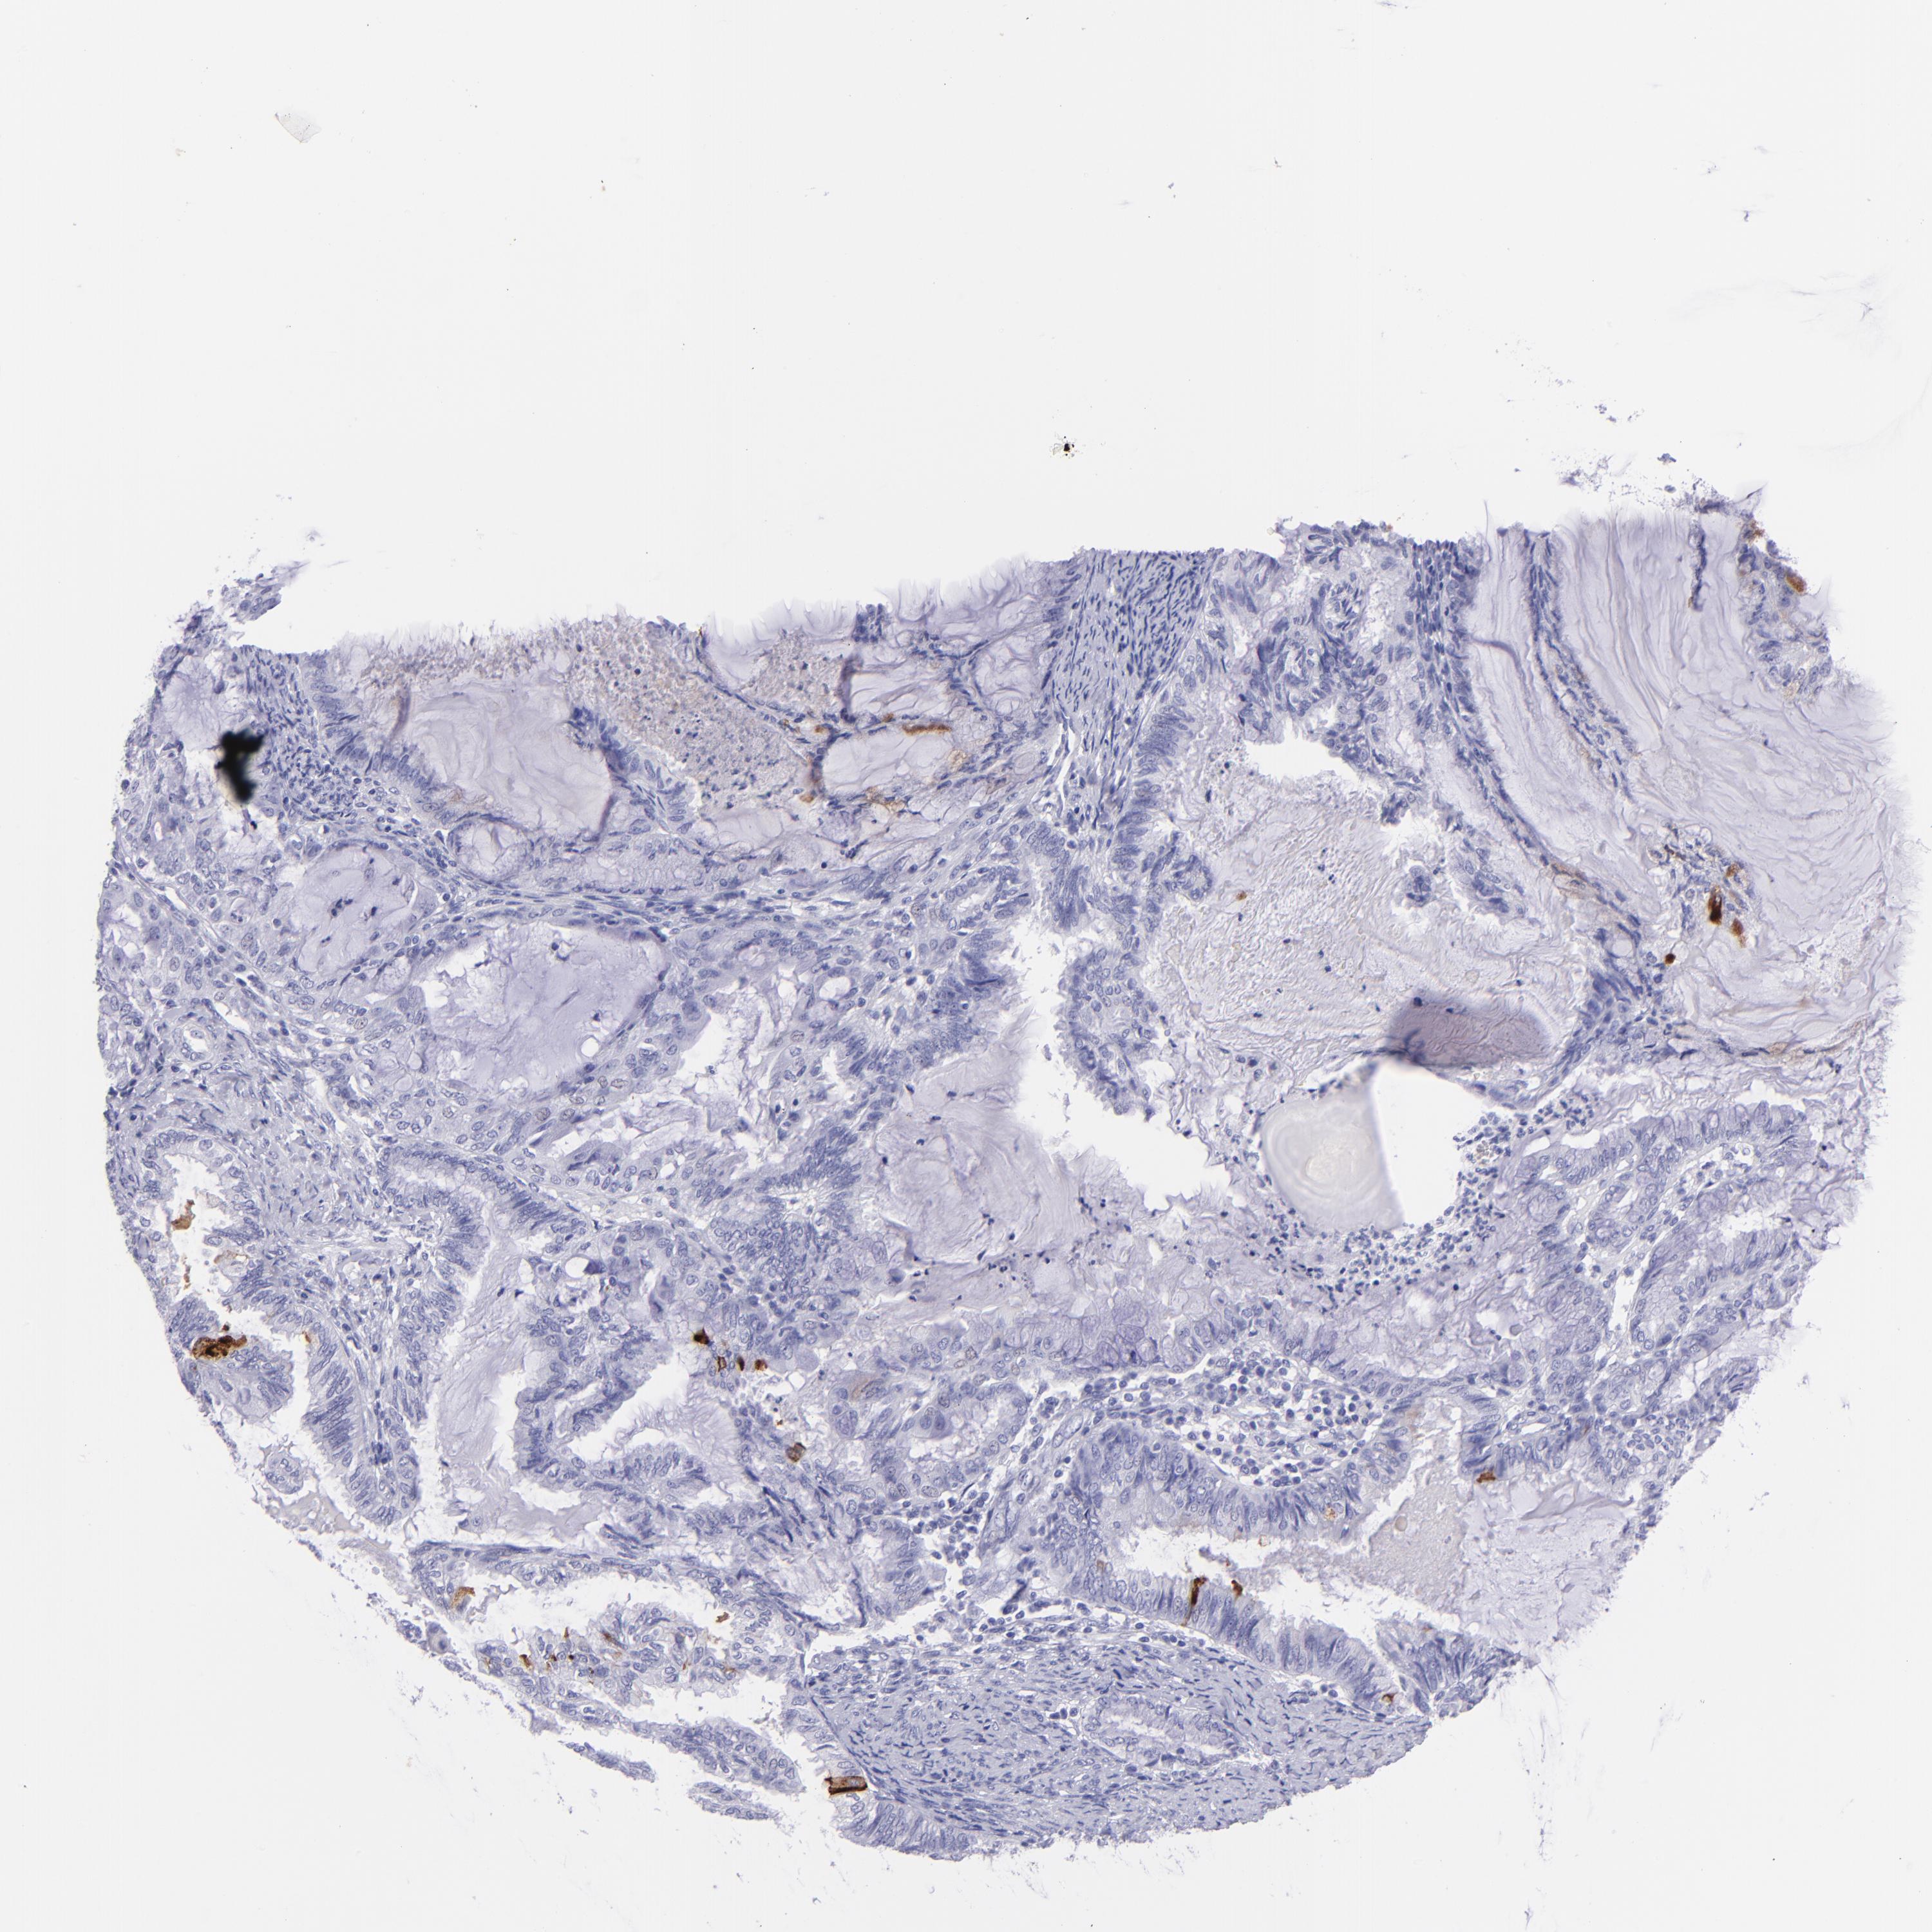

ENDOMETRIAL CANCER - Protein expressioni

A mouse-over function shows sample information and annotation data. Click on an image to view it in a full screen mode. Samples can be filtered based on level of antibody staining by selecting one or several of the following categories: high, medium, low and not detected. The assay and annotation is described here.

Note that samples used for immunohistochemistry by the Human Protein Atlas do not correspond to samples in the TCGA dataset.

Antibody stainingi

Antibody staining in the annotated cell types in the current human tissue is reported as not detected, low, medium, or high, based on conventional immunohistochemistry profiling in selected tissues. This score is based on the combination of the staining intensity and fraction of stained cells.

Each image is clickable and will lead to virtual microscopy that enables deeper exploration of all samples and also displays staining intensity scores, fraction scores and subcellular localization as well as patient and tissue information for each sample.

Antibody HPA009177

Antibody CAB002661

Staining

High

Medium

Low

Not detected

Intensity

Strong

Moderate

Weak

Negative

Quantity

>75%

75%-25%

<25%

None

Location

Nuclear

Cytoplasmic/membranous

Cytoplasmic/membranous,nuclear

Adenocarcinoma, NOS

Neoplasm, malignant, NOS